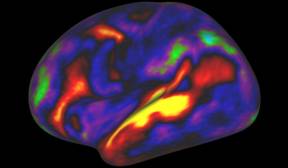

在一张未标明具体日期的资料图片中,扫描仪器中的脑部扫描显示了当人在听故事时大脑左半球的活动模式。在2016年7月20日,研究人员发表了一个壮观的图谱,这个图谱被众多专家称为神经科学的一个里程碑

计算机再次发现了这个奇特的区域,并且范?埃森及其同事发现当人们倾听故事时,该区域会变得异常活跃。这一发现显示:这个被他们称作55b的区域跟布罗卡氏区一样,是大脑语言网络的一部分。